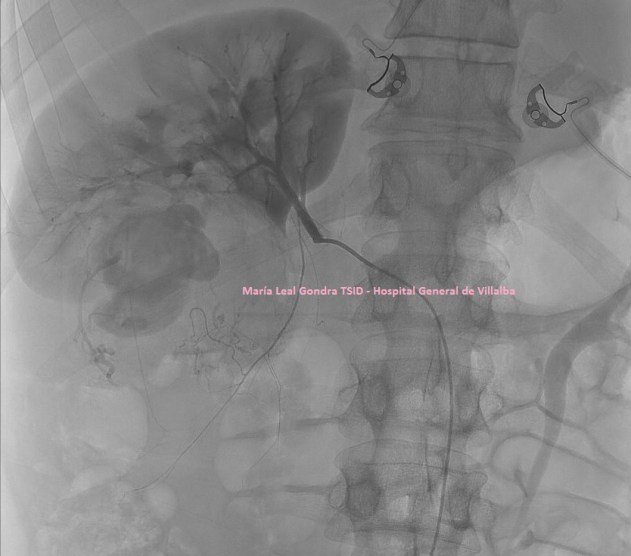

He comentado antes  que en ocasiones se le puede realizar a una paciente una galactografía, sobre todo cuando la secreción es por un solo conducto, y además sanguinolenta, pero es decisión de las doctoras, como ya he comentado. Esta prueba es la Galactografía, antes era muy habitual su realización, cada día más en desuso, te dejo la imagen 9 para que aprecies la belleza de esta técnica donde se usa un contraste que se inyecta previa canalización del agujero correspondiente al conducto que tiene la secreción, usando el mamógrafo para esta técnica.

9

10

Imagen 9 e imagen 10 son dos técnicas diferentes, que guardan una correlación muy evidente en la representación de los conductos galactóforos que van a buscar el pezón.